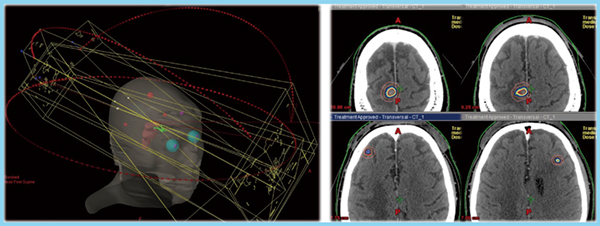

呼吸同期RapidArcは,肺がんの定位照射のほか,多発脳転移に対してきわめて有効である。図1は実際の症例であるが,4つの病変それぞれにアイソセンタを設定すると16門照射になるのに対し,シングルアイソセンタのRapidArcでは3arcですみ,線量分布も良好である。

図1 多発脳転移症例のシングルアイソセンタRapidArc